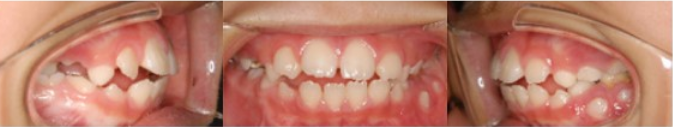

Pre-Ortho type 3. 반대교합 전용

8세남아 프리올소 착용 3개월 후

마지막 반대교합 전용 타입입니다.

교합을 맞물렸을 시 아랫니가 윗니를 덮은

상태이지만 이 프리올소로 거꾸로 물린 증상을

회복해 정상교합으로 도와주게 됩니다.